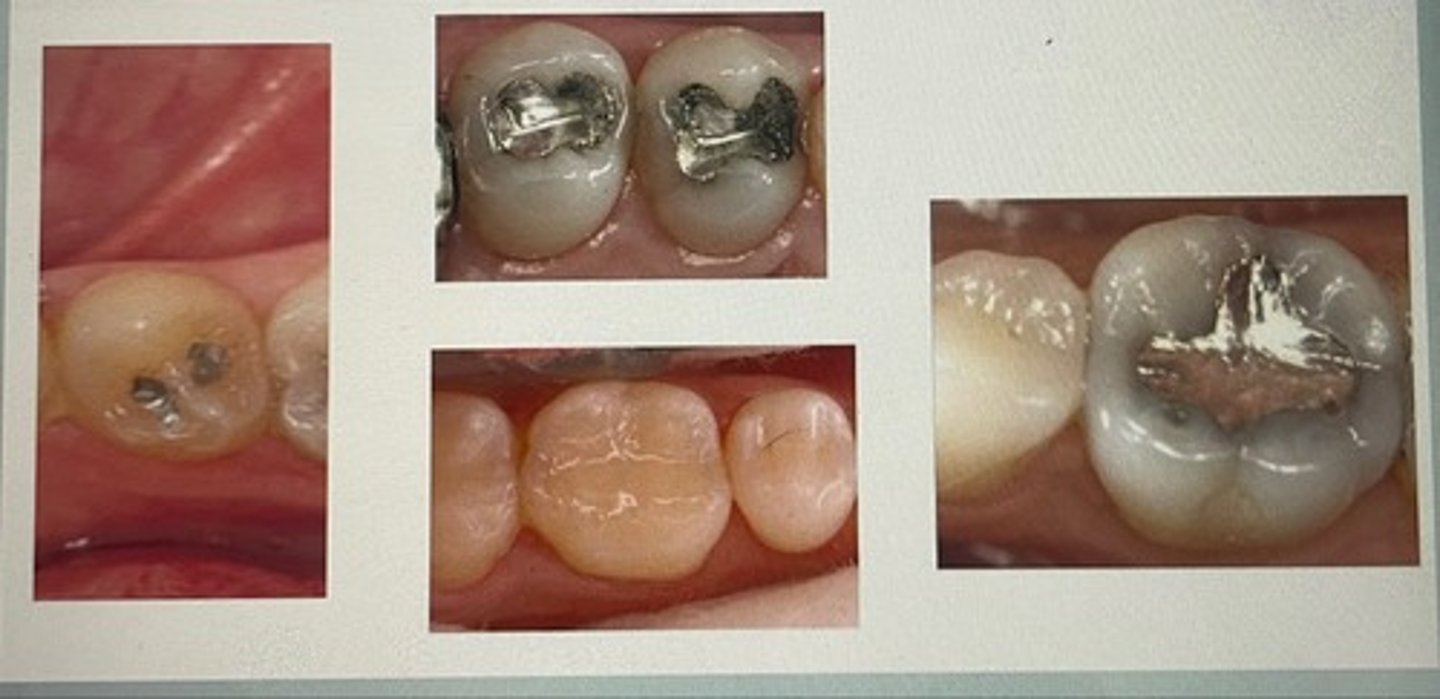

class I restoration

class II restoration